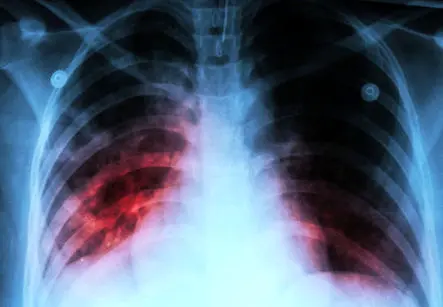

وی افزود: بیماری سل به وسیله یک باکتری ایجاد میشود؛ این باکتری به غیر از مو و ناخن که میتوان گفت بافت زنده نیستند، هر بافت زندهای در بدن را درگیر میکند و با توجه به محل و بافت درگیر شده علائم نیز طیف گستردهای خواهند داشت. از آنجایی که میکروب سل اکسیژن دوست است در ۸۰ تا ۸۵ درصد موارد ریهها را درگیر میکند در واقع شکل شایع بیماری سل، ریوی است. بنابراین شایعترین علائمی که برای بیماری وجود دارد، علائم تنفسی است؛ یعنی در سل ریوی شایعترین علامت سرفه طولانی مدت است. معنای این واژه به این صورت است که فرد حداقل دو هفته سرفه میکند. این سرفه هم میتواند با خلط همراه باشد و هم با خلط همراه نباشد.

ناصحی با اشاره به شباهت علائم بیماری سل به کووید۱۹، اظهار کرد: در پاندمی کووید۱۹ که همه افکار مردم و کادر درمانی مشغول این بیماری است، این احتمال وجود دارد که تشخیص برخی بیماران مسلول در سایه کرونا مغفول بماند. تنها تفاوت میان سل و کرونا این است که علائم سل ناگهانی و سریع نیست، اما در کرونا علائم به سرعت اتفاق میافتد و بیمار میتواند زمان دقیق آغاز سرفههایش را تخمین بزند. علیرغم موفقیتهای بسیار زیادی که در زمینه کنترل سل داشتیم؛ به طوری که اکنون کمتر از ۱۱ مورد در هر ۱۰۰ هزارنفر جمعیت بیماری سل دارند، اما هیچ استانی در کشور نیست که عاری از سل باشد. بنابراین هنگام شیوع بیماریهای تنفسی به سل نیز باید توجه شود.